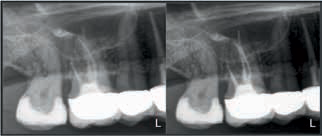

Z najnowszym aparatem Orthophos SL 3D, Twoja praktyka będzie przygotowana na każdy rodzaj leczenia. Przełomowa technologia sensora panoramy DCS oraz funkcja

Sharp Layer – zaspokoją potrzeby lekarzy, którzy wymagają maksimum szczegółów z obrazu panoramicznego. 3D daje Ci wybór pomiędzy objętością 11 cm x 10 cm, obrazująca pełne łuki szczęki i żuchwy wraz z sąsiadującymi strukturami, a 8 cm x 8 cm dająca wystarczającą ilość informacji diagnostycznych dla lekarzy ogólnych i implantologów.